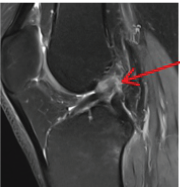

Plain radiographs of the right femur were obtained (Fig. 1), revealing a diaphyseal mid-third fracture with a simple fracture line located immediately distal to the previous osteosynthesis material, cortical thinning was noted without pathological lesions.

Figure 1: Anteroposterior (AP) X-ray of the right femur, February 26, 2025. AP radiograph of the right femur showing a displaced periprosthetic femoral fracture with varus angulation, displacement, and shortening (red arrows). Previous osteosynthesis material is visible without signs of fatigue or loosening (star). Adequate corticomedullary differentiation is observed in the diaphyseal region, along with cortical thinning (green arrows).